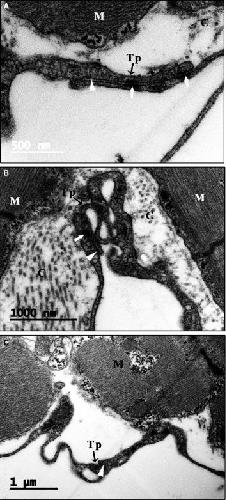

Figure 3. Distribution of CTs in the upper region, middle region and base of the Xenopus tropicalis myocardium. CTs mainly concentrated on the outer surface of trabeculae containing cardiomyocytes in the upper region (A), middle region (B) and base (C) of the X tropicalis myocardium. Most of the trabeculae are twined around one, two or several CTs and their telopodes or with telopodes alone. Aâ², Bâ² and Câ²: CTs of A, B and C that are not included in the trabecular structure; CT: Cardiac telocyte; Scale bar: Size as shown in the figures; Tr: Trabecula of the myocardium |

Fig. S4: Distribution of CTs among trabeculae in the X. tropicalis myocardium. Among the trabeculae, CTs twined around the outer surface are able to connect using their telopodes in the upper region (A), middle region (B) and base (C). Scale bar: Size as shown in the figures. CT: Cardiac telocyte. Tr: Trabecula of myocardium. |